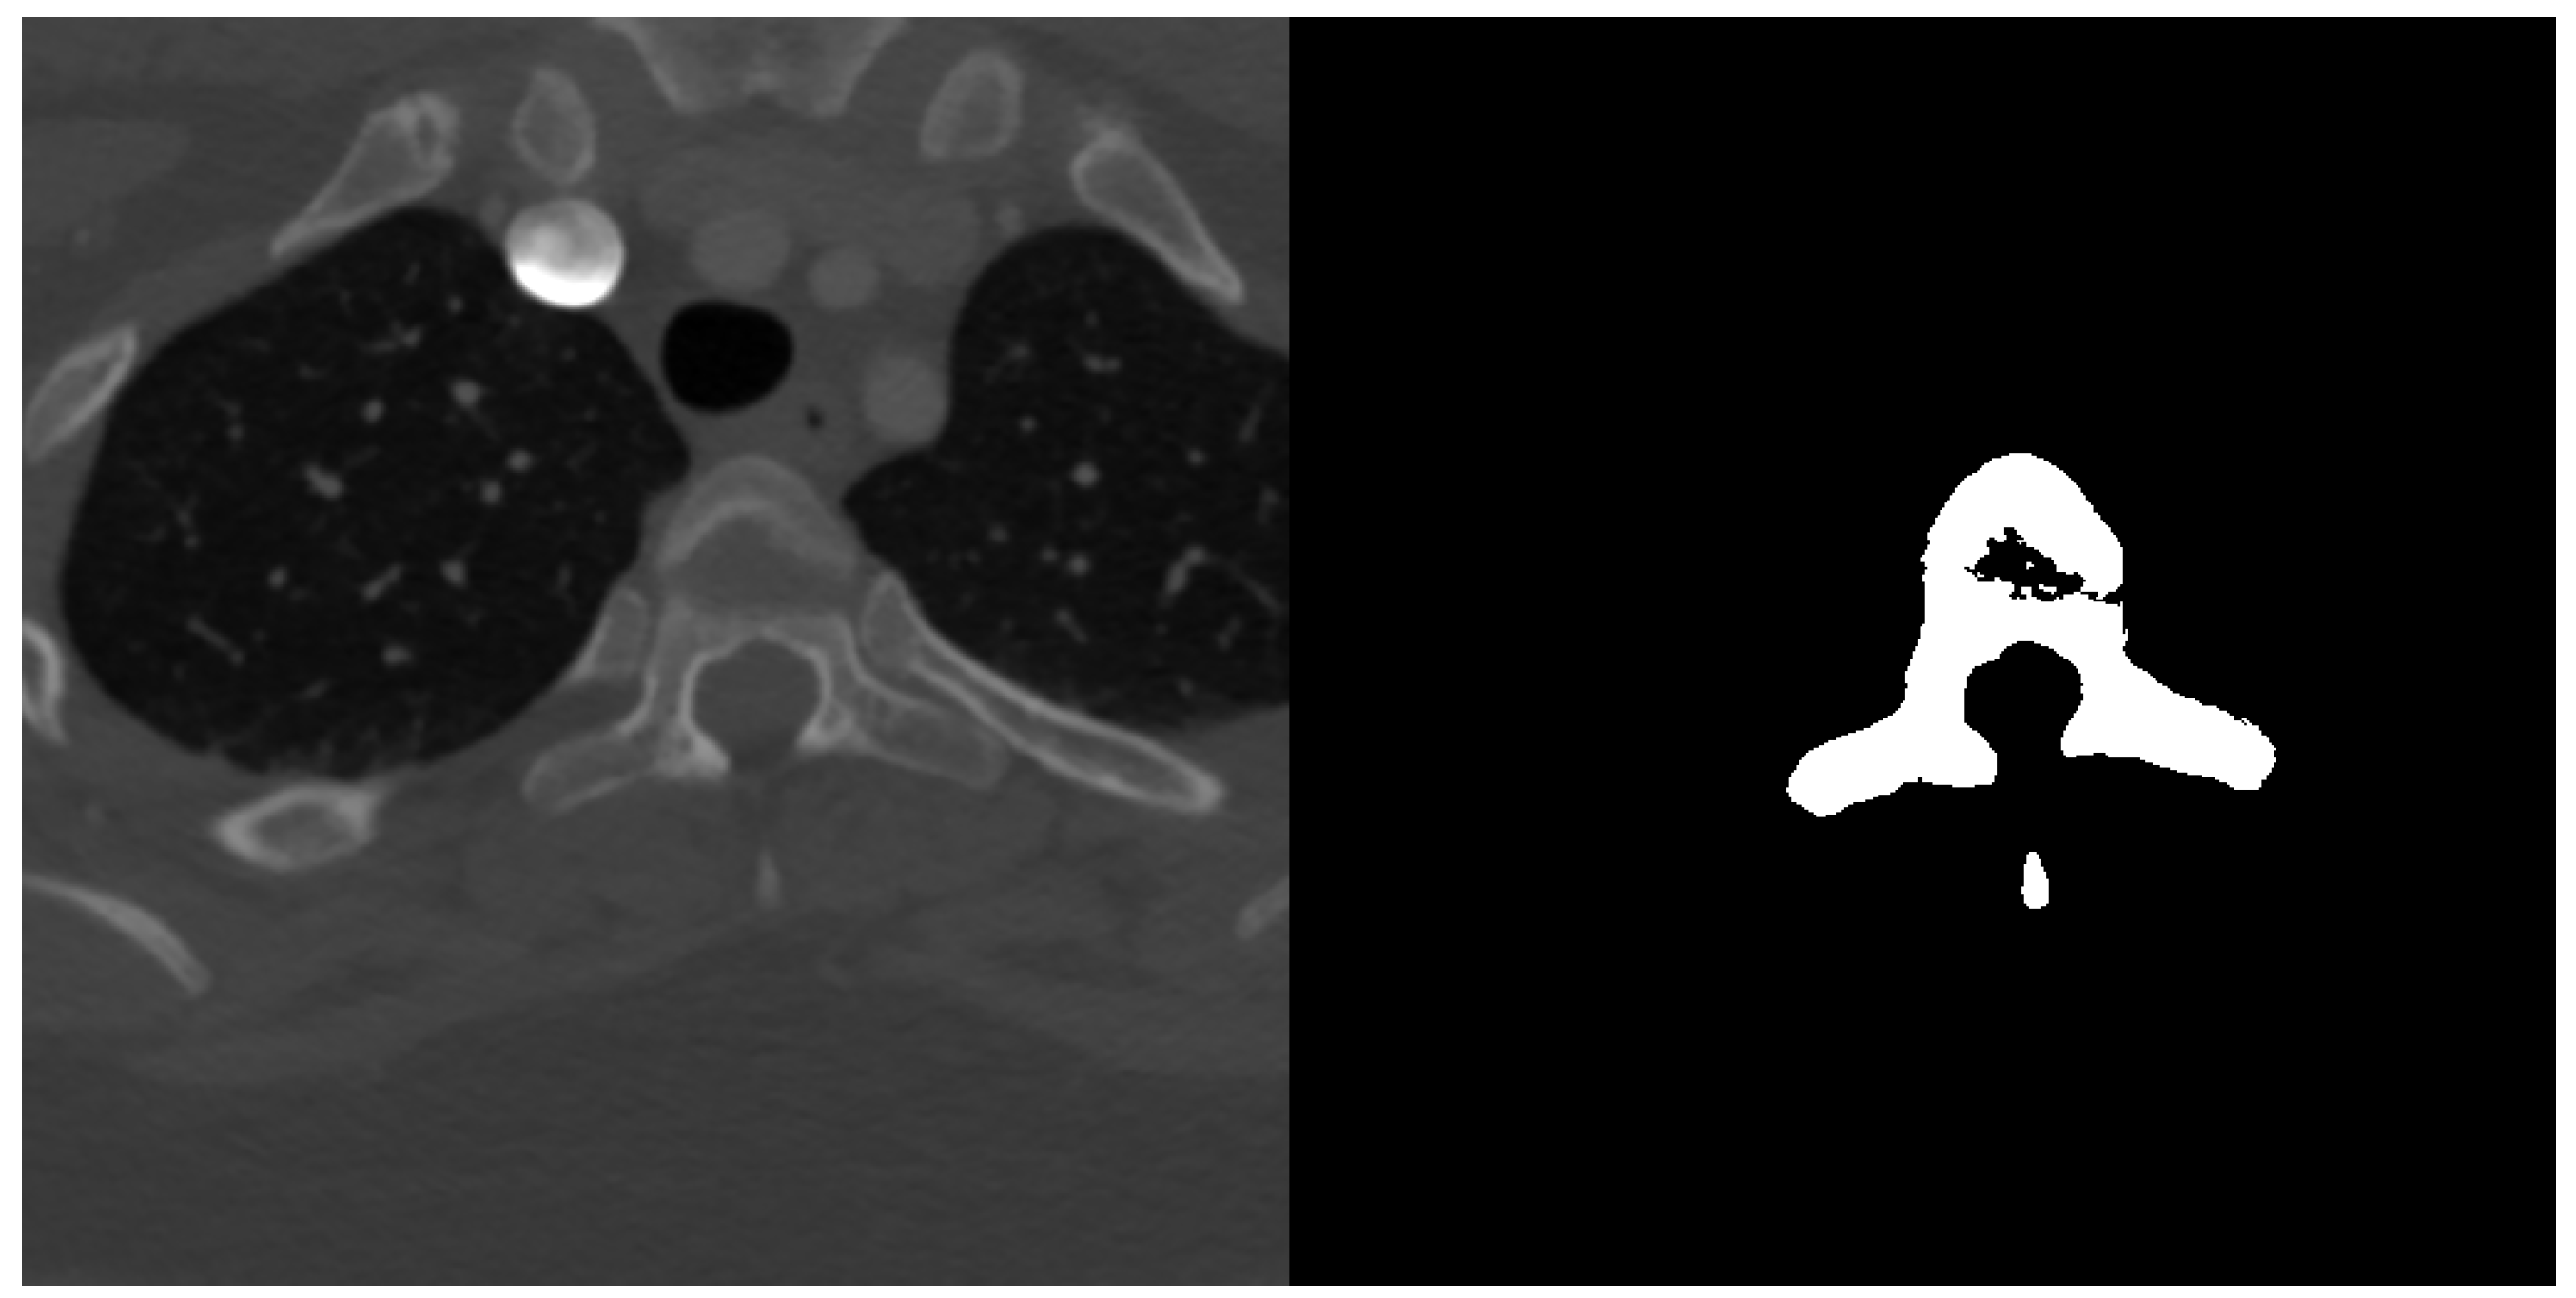

2.1.3. Spine Dataset

Spine dataset consists of 10 CT scans of different patients in the age 16–35 years old. The pictures had resolution pixels and were provided in NRRD format. Number of slices in each scan was in range from 520 to 600 slices in the third dimension. Scans cover lumbar and thoracic spine region and were acquired without intravenous contrast. Slice thickness is 1 mm per slice and the in-plane resolution is between 0.31 and 0.45 mm. The data have been acquired at the Department of Radiological Sciences, University of California, Irvine, School of Medicine and scanners used include Philips or Siemens multidetector. Data were published as a part of 2014 CSI workshop challenge of the web http://spineweb.digitalimaginggroup.ca. Dataset can be used for development, training and evaluation of spine segmentation algorithms. Image data are provided in NRRD format. An example image slice and according ground truth mask can be seen in Figure 3.

Figure 3.

Example transversal image slice from spine dataset (left) with according ground truth mask (right).

Ground truth segmentation masks have been semi-automatically segmented and verified for complete thoracic and lumbar vertebrae for each scan. Segmentation masks are also stored in NRRD filed and originally each vertebra had assigned different label. The first vertebra was labelled as 100, the second as 200 and so on. For the semantic binary volumetric segmentation task the masks have been thresholded to greyscale 8bit PNG files and had format where vertebrae tissue was assigned with a value of 255 and non-vertebrae tissue with the value 0 [19].